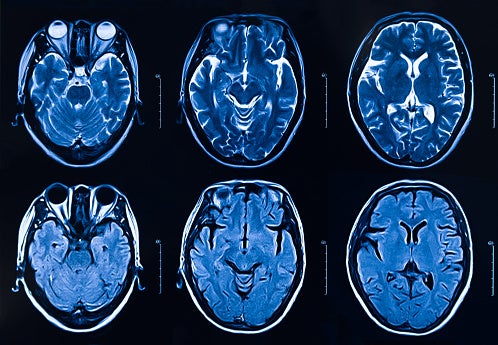

중풍으로도 불리는 뇌경색은 대표적인 뇌혈관질환입니다. 뇌혈관은 정상적인 뇌 활동에 필요한 산소와 영양분을 공급하는 혈액의 통로로 혈관이 막히거나 터지면 뇌 일부가 손상됩니다.

뇌는 한번 손상되면 재생이 어려운 신체기관 중 하나입니다. 따라서, 혈관을 통한 산소와 영양분 공급이 원활히 이뤄지지 않으면 생명을 위협할 수 있어 각별한 주의가 필요합니다. 뇌졸중은 뇌에 혈액을 공급하는 혈관이 막혀 발생하는 뇌경색과 혈관이 터져 발생하는 뇌출혈로 구분됩니다.

뇌경색은 동맥경화증에 의한 혈관 협착과 심장 등에서 떨어진 혈괴가 뇌혈관을 막을 때 발생합니다.

사진 픽사베이